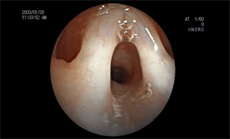

内窥镜智能影像识别